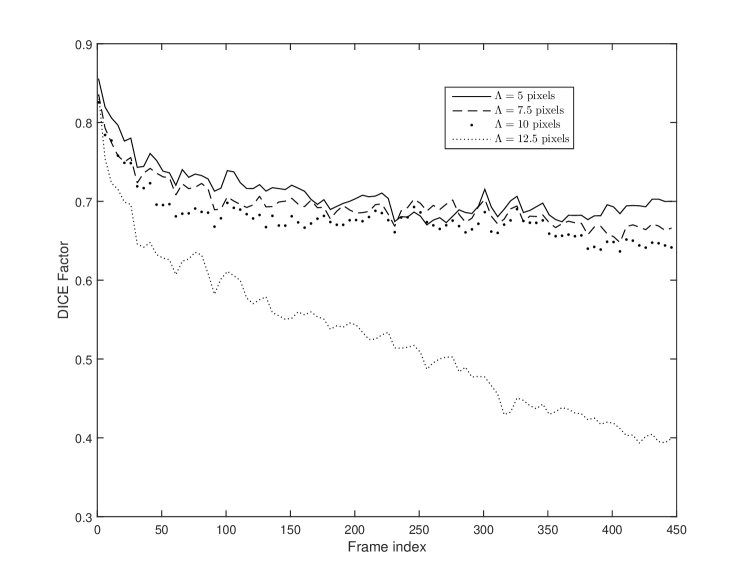

Here, we study the effect of contour points spacing on the accuracy of the Ad-PAC algorithm. In this study, after segmentation of each frame, the contour is re-sampled and the new value of is chosen to be , where is the perimeter of the segmented contour, and is the contour points spacing. Fig. 11 presents the average DICE factor obtained from all videos for different values of . From this figure, one can see that the average DICE factor degrades quickly when the contour spacing is large and it improves when the contour spacing decreases but it nears saturation at pixels.